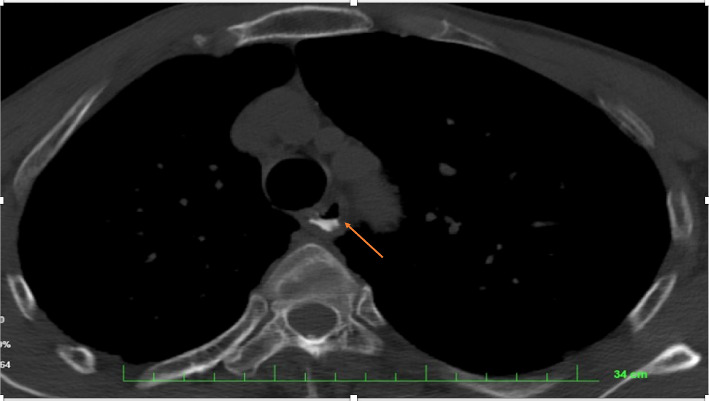

Introduction: Hypopharyngeal rupture caused by indirect neck trauma is a rare but potentially life-threatening injury. Delayed diagnosis can lead to severe complications, highlighting the importance of clinical suspicion and appropriate imaging. Case Presentation: A 64-year-old male patient sustained indirect neck trauma following a car accident. He was initially transferred to the hospital with mild symptoms and was discharged. However, a few hours later, he returned to the emergency department with neck pain, odynophagia, and dysphagia. CT imaging revealed evidence of hypopharyngeal rupture accompanied by retropharyngeal emphysema. The patient was managed conservatively with Nil Per Os (NPO), intravenous antibiotics, and the placement of a nasogastric (NG) tube. He achieved full recovery without complications. Conclusion: This case emphasizes the importance of thoroughly evaluating the relationship between clinical complaints and the mechanism of injury in patients with indirect neck trauma. High clinical suspicion, detailed history-taking, and appropriate imaging modalities are crucial for early diagnosis and effective management.